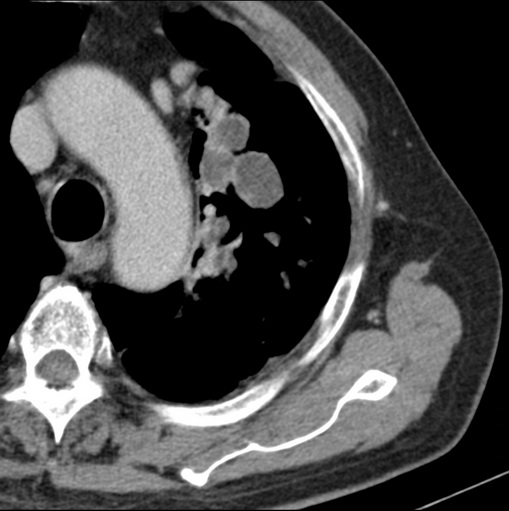

男性患者 81岁 咳嗽 咳痰 咯血

左肺中心型肺癌并:1.左肺阻塞性肺炎;2.纵隔淋巴结肿大;

肿块贴近左肺门,包绕左上肺动脉,形态不规则。肿块增强扫描中度强化。纵膈内主动脉弓左旁间隙、气管隆突前、下间隙见多枚淋巴结影。综上考虑左侧中央型肺癌可能性大。图片没有完整上传,尤其是左肺上叶支气管分支层面没有上传,因此不好判断是叶支气管中断还是段支气管中断。另外,下图红色部分所示是“黏液支气管征”吗?